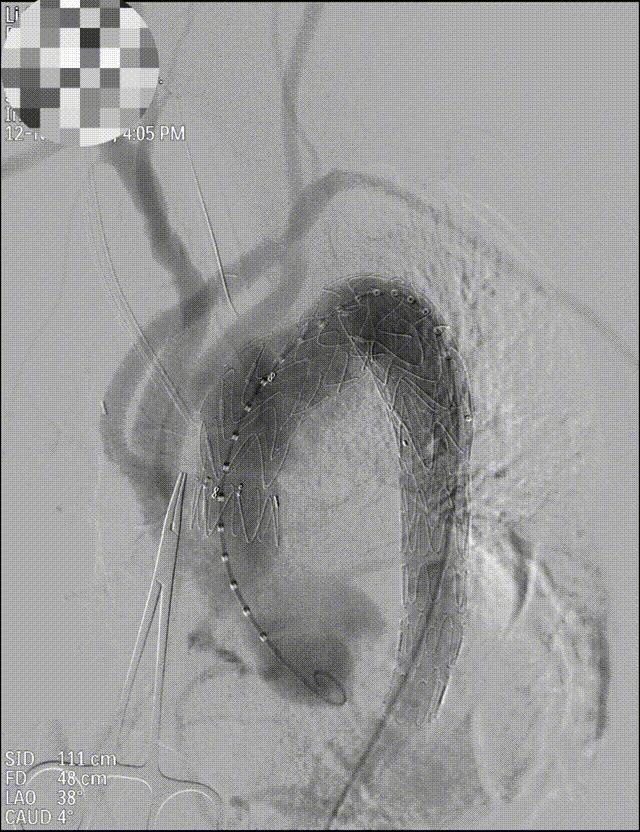

人工血管+介入支架,杂交手术